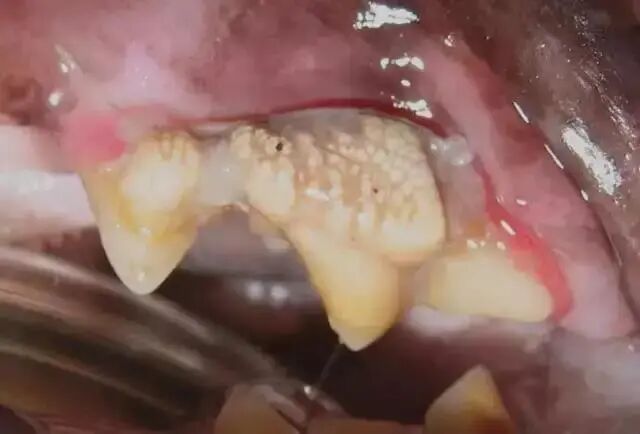

5级

牙的残迹模糊只有牙的影子,牙龈已覆盖原来牙冠的位置